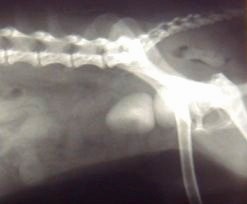

飲み込んだ「画鋲」 |

→↑が飲み込んだ「画鋲」です。   ←はマイクロチップです。

犬 : マルチーズ オス 3歳 体重4Kg